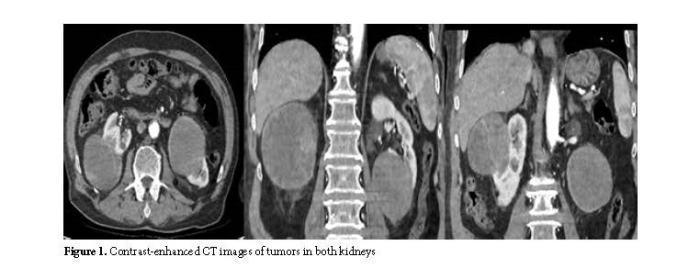

A 76-year-old white male patient was referred to our clinic after bilateral renal masses were detected during an evaluation for flank pain. His medical history included coronary artery disease and a 50 pack-year smoking history. There was no family history of genitourinary cancer. Physical examination revealed a palpable mass in the right flank region. Laboratory tests, including complete blood count, basic metabolic profile, and liver function tests, were within normal limits. Preoperative creatinine level was 1.2 mg/dL. Contrast-enhanced computed tomography (CT) of the entire abdomen showed a mass measuring 94x81 mm in the posterolateral region of the right kidney and another mass measuring 79x75 mm extending from the lower pole to the renal hilum of the left kidney (RCC?) (Figure 1). Contrast-enhanced abdominal and thoracic computed tomography (CT) scans were performed to evaluate for metastasis. No metastatic lesions were detected on imaging.